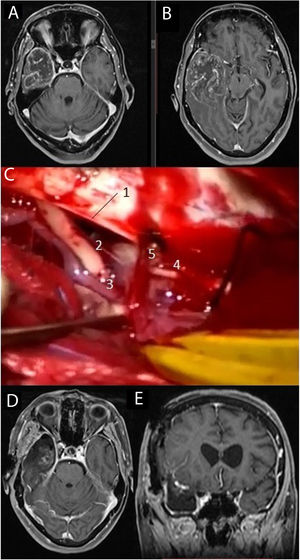

Imágenes de resonancia magnética en la secuencia T1 con contraste intravenoso (A, B) que muestran una voluminosa tumoración situada en el lóbulo temporal derecho, correspondiente a glioblastoma. Se practicó una lobectomía temporal (C), en la cual pueden diferenciarse el borde libre del tentorio (1), el III par craneal derecho (2), la arteria comunicante posterior derecha (3), el IV par craneal derecho (4) junto a una vena cortical que drena en el tentorio (5). Las imágenes D y E muestran respectivamente los cortes axial y coronal de la resonancia magnética postoperatoria.

Se recogieron los datos pertenecientes a la edad, sexo, fecha de diagnóstico, Karnofsky Performance Status (KPS), enfoque terapéutico con o sin cirugía y modalidad de esta, intervalo libre de progresión desde la cirugía inicial, número de intervenciones, modalidad de tratamiento adyuvante y causa del fallecimiento. Del mismo modo, se obtuvieron de las imágenes e informes radiológicos los datos relacionados con la presencia de tumor en región elocuente, considerando como tal la extensión del tumor a la región tálamo-capsular, corona radiata o centro semioval, lóbulo central, áreas relacionadas con el lenguaje (opérculo frontal del hemisferio dominante, circunvolución supramarginal, lóbulo temporal dominante y transición entre dichas zonas). Para la extirpación de los tumores en dichas localizaciones se contó con la ayuda de monitorización neurofisiológica intraoperatoria (fig. 1) o cirugía con paciente despierto (fig. 2) con el fin de maximizar el grado de extirpación y limitar el riesgo de déficit neurológico postoperatorio (fig. 3).